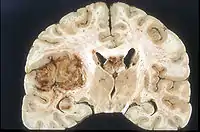

Examen macroscópico

A pesar de la corta duración de los síntomas, los glioblastomas suelen ser grandes en el momento de la presentación y pueden ocupar más de un lóbulo. La lesión es en general unilateral, aunque las del tronco cerebral y el cuerpo calloso pueden tener simetría bilateral. El tumor ocupa la misma posición en los dos hemisferios y muestra un aspecto de "mariposa". La extensión supratentorial bilateral se debe a un rápido crecimiento a lo largo de las estructuras mielinizadas, en particular a través del cuerpo calloso y a lo largo del fórnix hacia los lóbulos temporales. Los límites de la masa neoplásica, que no está encapsulada, son difusos por todas partes. La coloración es grisácea, pero pueden encontrarse abundantes variaciones de color, causadas por necrosis o hemorragias más o menos recientes, por lo que sobre el fondo gris aparecen zonas amarillentas, por degeneración grasa o necrosis y zonas de color rojizo o negruzco debidas a hemorragia.

La zona periférica del tejido tumoral hipercelular aparece como un borde suave y gris. El tejido necrótico puede bordear estructuras cerebrales adyacentes sin una zona tumoral intermedia detectable macroscópicamente. La necrosis central puede ocupar más del 80 % de la masa total del tumor.

Los glioblastomas están generalmente salpicados de manchas rojas y marrones debidas al sangrado. A veces son lo suficientemente grandes como para causar síntomas similares a un accidente cerebrovascular, que puede ser el primer signo clínico del tumor. Los quistes macroscópicos, cuando están presentes, contienen un fluido turbio proveniente del tejido tumoral necrótico licuado, en claro contraste con los quistes de retención bien definidos de los astrocitomas difusos de grado II.

La mayoría de los glioblastomas de los hemisferios cerebrales son claramente intraparenquimatosos, con epicentro en la materia blanca. A veces la neoplasia se presenta como ampliamente superficial y en contacto con leptomeninge y duramadre, y se puede confundir con un carcinoma metastásico o con una lesión extra-axial, como el meningioma.[11][60]